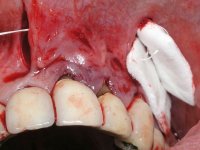

TREATMENT NOTES:

I have decided to replace the old fixed partial dentures to improve aesthetics and simultaneously eliminate root exposures. In order to do so, periodontal plastic surgery – tunneling procedure - was a priority, to increase the thickness of the soft-tissue and to do a coronal repositioning to reduce the root exposures.

PERIODONTAL PLASTIC SURGERY:

Dr. Manuel Neves, Clínica Dr. Manuel Neves.